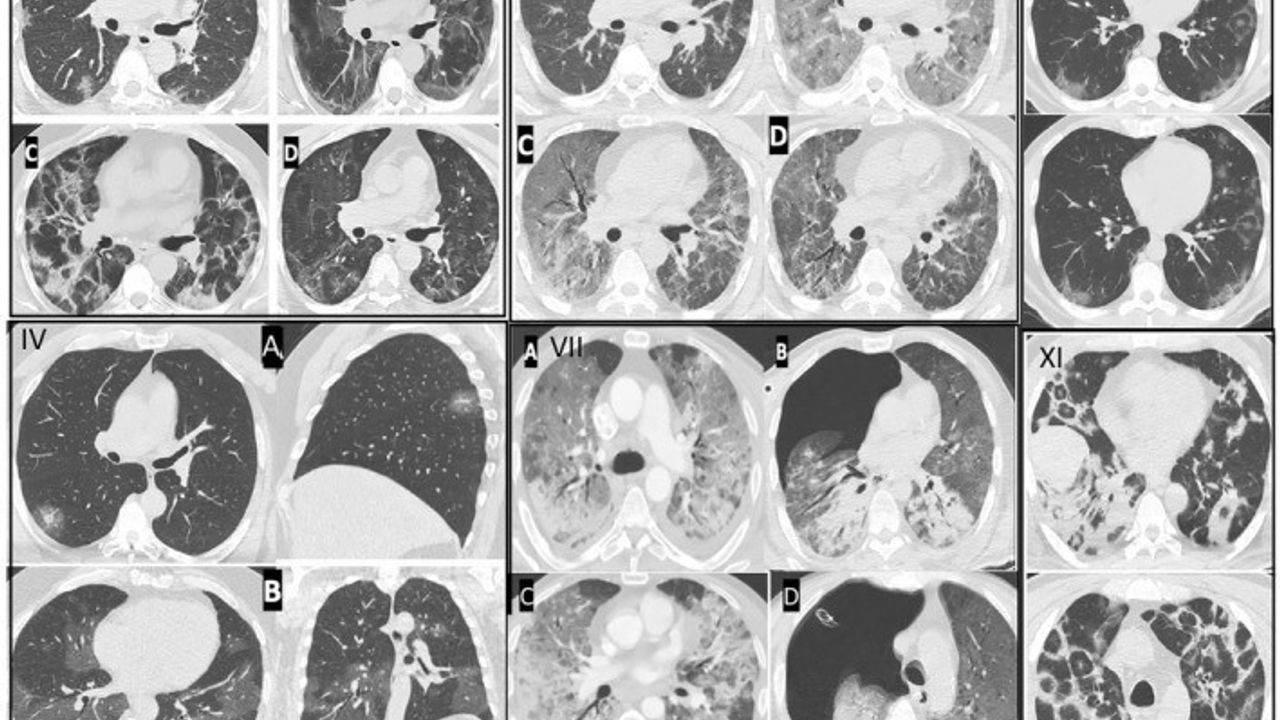

Kovid-19’un, özellikle kılcal damarlar üzerinde ciddi yaralar açtığını söyleyen Özkaya, "Pandemi sırasında takip ettiğimiz binlerce hastada, endotelit adı verilen damar iç yüzeyindeki hasarın ani ölümlere yol açtığını gözlemledik ve bu bulgularımızı uluslararası dergilerde paylaştık. Avrupa Kalp Dergisi’nin son verilerinde de Kovid-19 sonrası damar yaşlanmasının hızlandığı ifade edilmiştir" şeklinde konuştu.